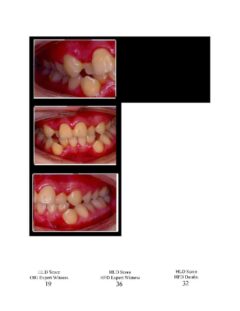

So here again are photos of children’s teeth that were pre-approved for treatment by the state’s Medicaid claims administrator TMHP/ACS, that HHSC-OIG now claims were fraudulently scored by Medicaid dental providers. These cases are from the SOAH hearings that have been completed for Harlingen Family Dentistry and Antoine Dental Center. The SOAH courts found both practices innocent of any allegation of Medicaid fraud or misrepresentation. The photo pages show the attending dentist’s HLD score, the dentist’s expert witness score and the OIG expert’s score.

Antoine Dental Center